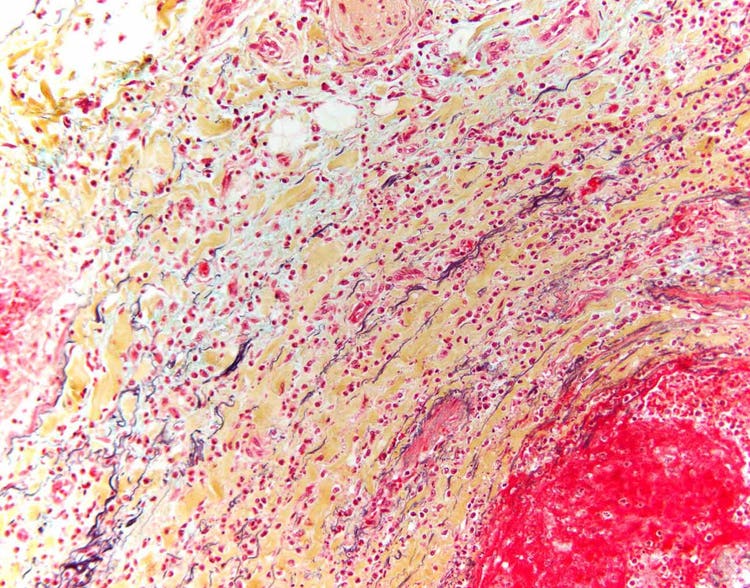

Trichromfärbung des Herzens unter dem Mikroskop

Schnitt durch ein geschädigtes menschliches Herz nach Trichromfärbung. Blaue Bereiche sind Narbengewebe. Rote Bereiche sind lebensfähige Zellen. Aufgenommen mit einem Olympus BX43 Mikroskop und einer DP26 Kamera. Bildquelle: Dr. Marianne Hamel.